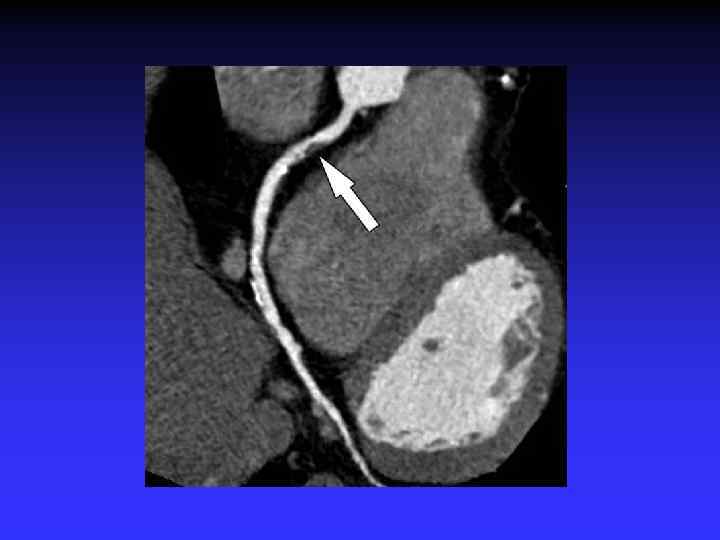

Coronary CTA